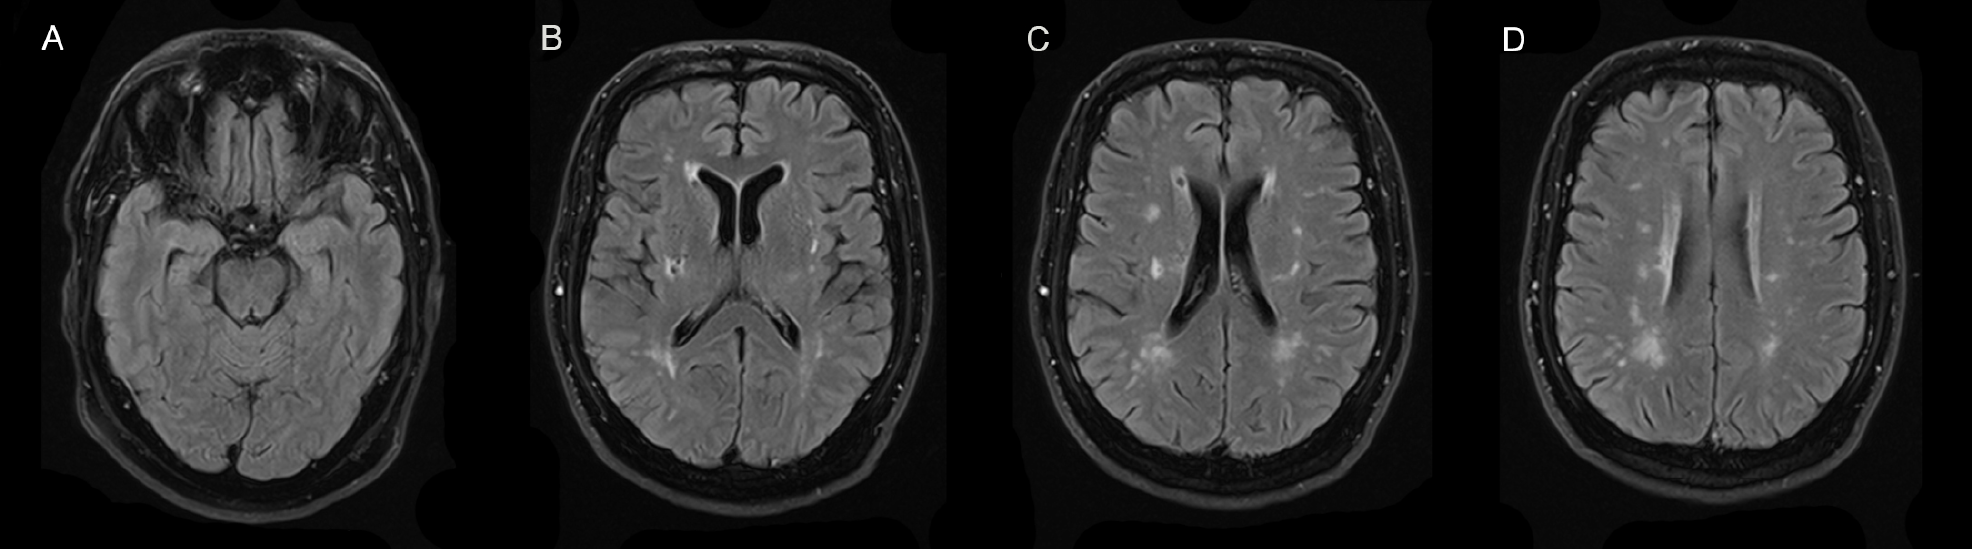

Een MRI-scan van de hersenen op 55-jarige leeftijd toonde multipele, deels confluerende WSL periventriculair en in de diepe witte stof (fazekasscore 2) alsook verschillende lacunaire infarcten (figuur 1). Er was geen aantasting ter hoogte van de temporaalkwab.

Figuur 1. FLAIR-gewogen MRI-beelden van patiënt A

Axiale snedes door: A. temporaal- en occipitaalkwab, B. basale ganglia, thalamus en capsula interna en externa, C. corona radiata, D. centrum semiovale. Confluerende periventriculaire en diepe wittestofletsels (fazekasscore 2) en lacunaire infarcten enkel gevisualiseerd ter hoogte van B, C en D. Geen wittestofletsels ter hoogte van de anterieure temporaalkwab, zoals verwacht bij het ‘klassiek’ CADASIL-syndroom.